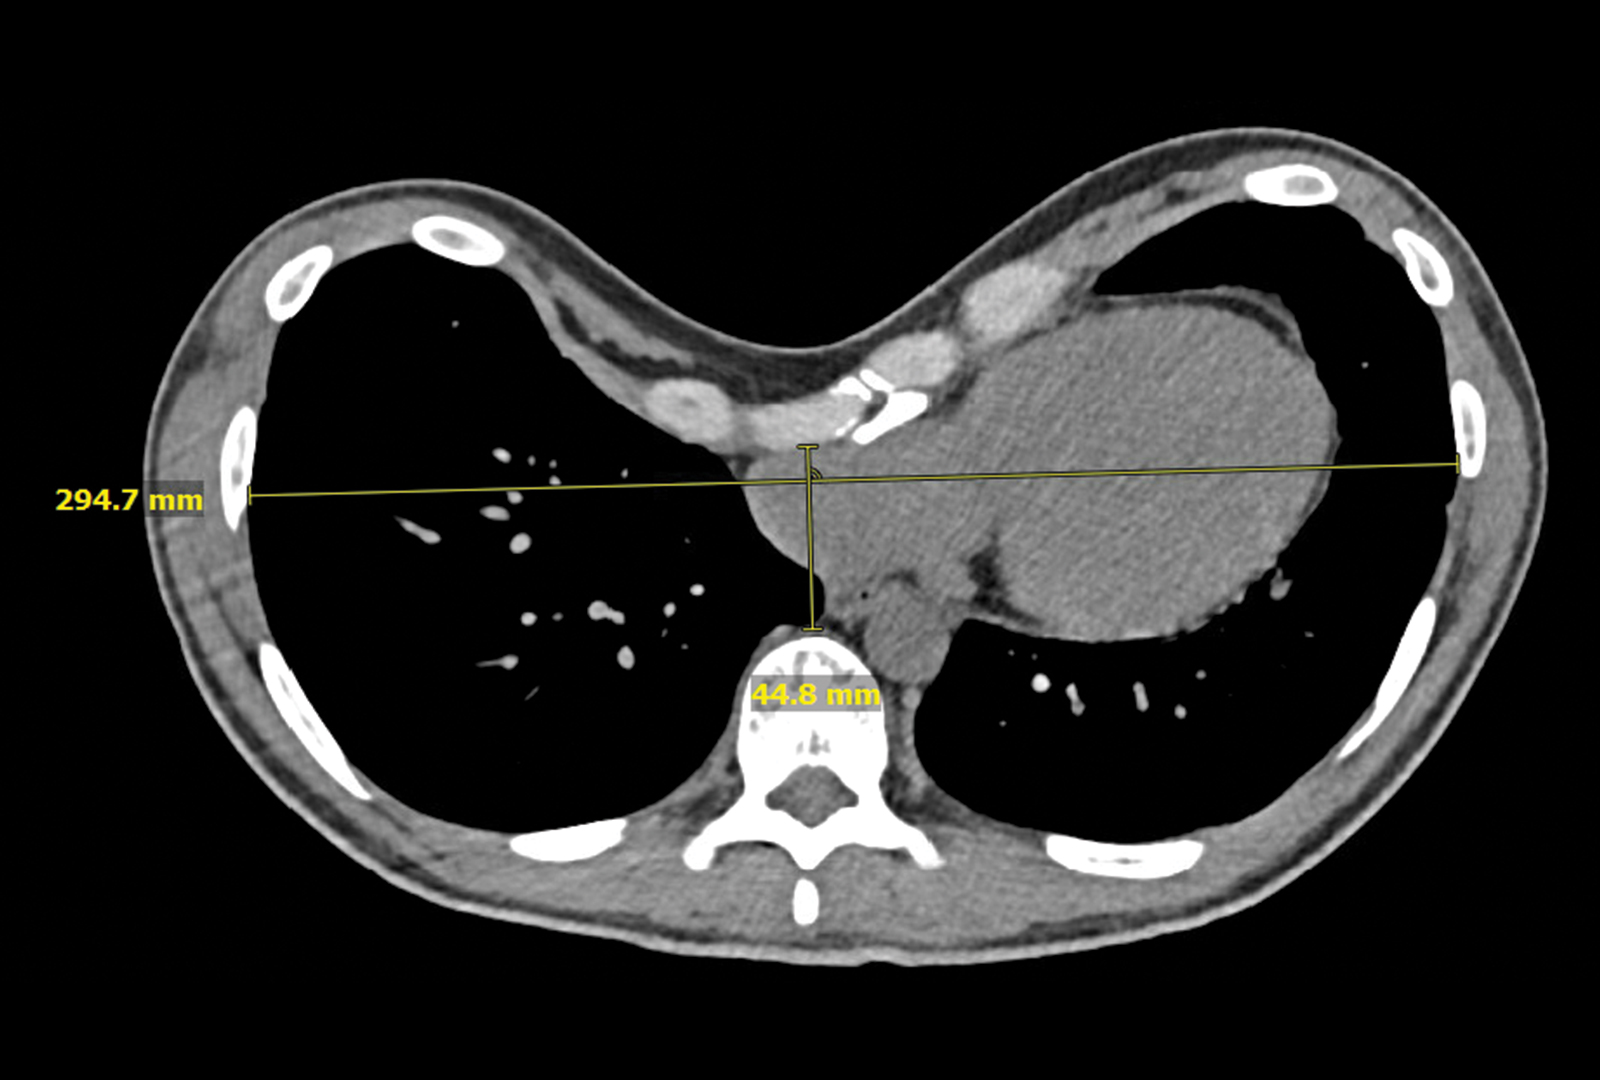

The patient was reporting intermittent palpitations, chest pain, worsening shortness of breath with activity, and decreased exercise tolerance. “With a Haller Index of 6.5, the severity of the chest deformity was compressing the patient’s right atrium and ventricle, and limiting full lung expansion,” Dr. Bizekis says.

After carefully reviewing the patient’s chest CT imaging, he recommended the minimally invasive Nuss procedure.

Preoperative chest CT of the patient’s pectus excavatum. Source: NYU Langone Health